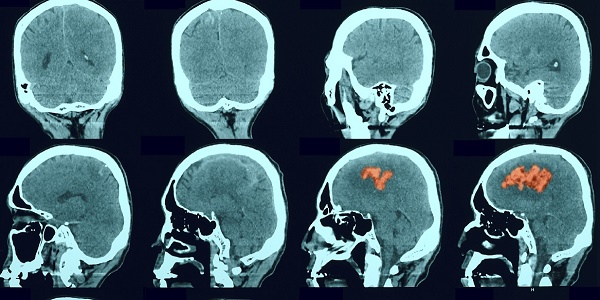

The aim of the Stroke Research Group is to share the latest stroke research and encourage collaborations between researchers and within various disciplines.